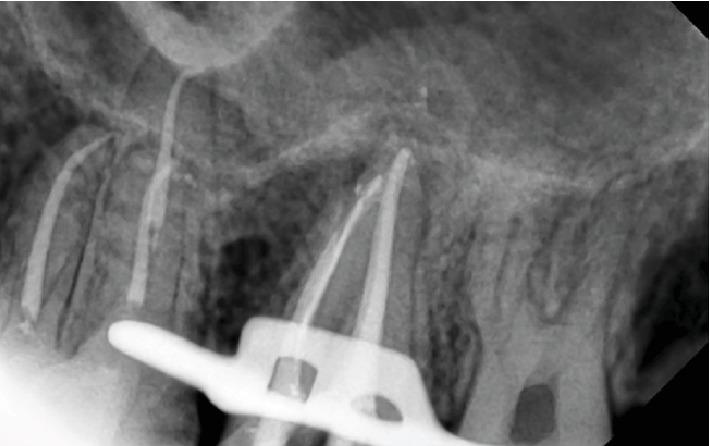

This case report illustrates the recovery of dizziness of a young healthy patient after root canal therapy of upper second molar. The patient developed dizziness and unbalanced walking four months ago. After cardiac, ENT, neurological, physiotherapy and medical investigations, his entire checkup showed no abnormalities. The patient visited a dental clinic for a routine checkup; after dental clinical and radiographical examination, a chronic abscess infection in an upper second molar region close to the sinus was diagnosed. Root canal therapy was performed that resulted in a disappearance of the dizziness and full recovery was achieved. Infected upper teeth with periapical lesion are associated with dizziness as a complication of odontogenic-related sinusitis. Dental and medical cooperation contributes to a better management diagnosis of the dizziness.

本病例报告阐述了一名年轻健康患者在上颌第二磨牙根管治疗后头晕症状的恢复情况。该患者四个月前出现头晕及行走不稳症状。在进行心脏、耳鼻喉、神经、物理治疗及医学检查后,其全面检查未发现异常。患者前往牙科诊所进行常规检查;经牙科临床及影像学检查,诊断出上颌第二磨牙区域靠近鼻窦处存在慢性脓肿感染。进行根管治疗后,头晕症状消失,患者完全康复。患有根尖周病变的感染上颌牙齿与作为牙源性鼻窦炎并发症的头晕有关。牙科与医学合作有助于更好地诊断和处理头晕症状。